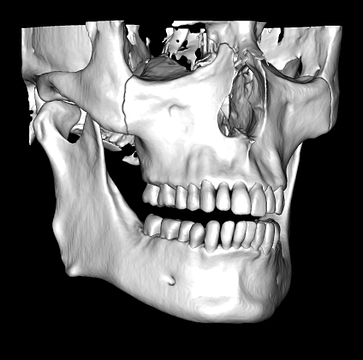

So what is Segmentation? It basically means taking the CBCT and delineating all the different 3D structures, bones, individual teeth, etc.

These can then be individually exported via the software by generating STL files from CBCT dicom data. This can be used in other dental software. Jaw STLs can be used in Modjaw (jaw motion capture) for TMJ analysis, for example. As well as in exocad to help visualize the jaws for surgical planning or guide creation.

Being able to take a DICOM file and turn it into STLs is useful for a host of different CAD/CAM indications.

CBCT Segmentation into STL

Generate STL files from CBCT DICOM data.

Generate maxilla and mandible in one STL file or face, teeth, maxilla, mandible, airway, cranial base, canals as separate STL files.